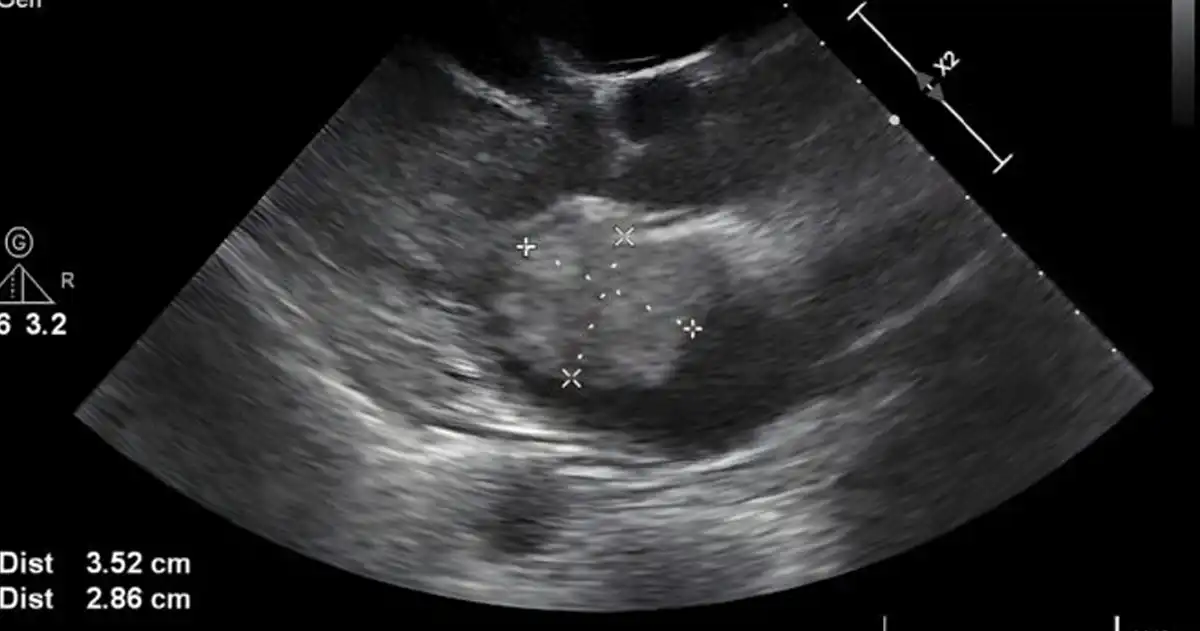

“She asked me whose hand that was,” Amanda recalled. The scan appeared to show a large hand cradling Kyler’s head. Amanda shared the image on Facebook, saying it brought her to tears: “It looks like a hand holding his head.”

Whether seen as a sign of divine protection or simply a comforting coincidence, the image deeply moved Amanda—and many others online.